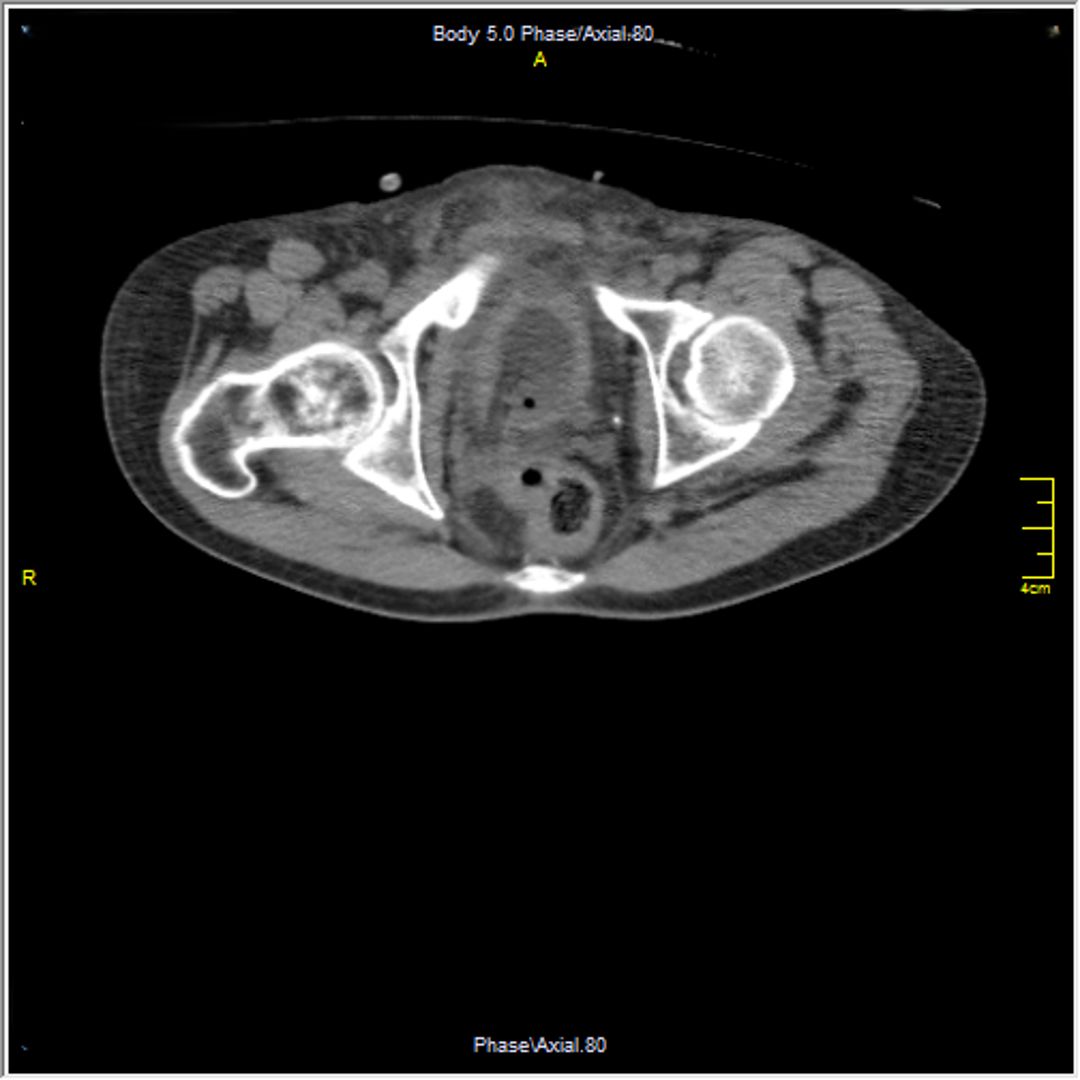

A 23-year-old male with a history of traumatic spinal cord injury (T3 ASIA A), iatrogenic urethral stenosis limiting clean intermittent catheterization (CIC), and low bladder capacity, was admitted for a planned open cystostomy and bladder stone extraction. Following stone removal, a 24-French SPC was placed. On postoperative day 3, the patient developed AD, characterized by hypertensive urgency and profuse sweating. Renal ultrasound revealed right-sided hydronephrosis. A CT scan confirmed SPC misplacement, with the catheter tip located inside the right distal ureter.

Figure 1 Axial view of the SPC's tip in the distal right ureter

Figure 3 Axial view of the SPC's tip in the distal right ureter